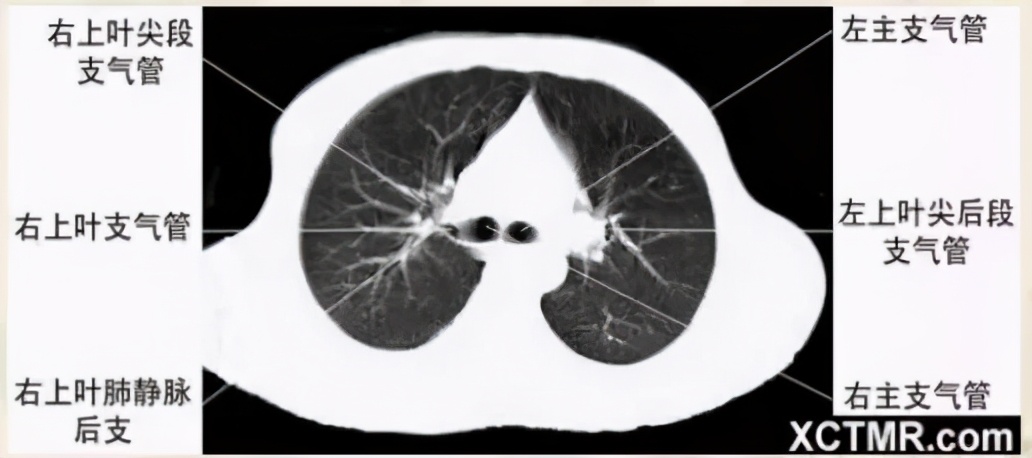

右上叶支气管层面